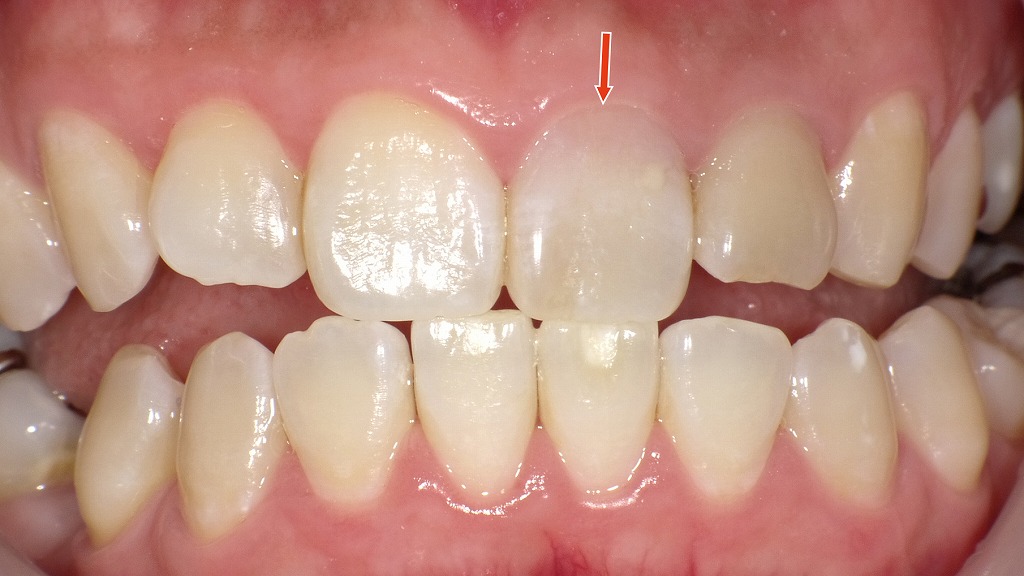

◆ホワイトニング後の口腔内写真

ホワイトニングにより、矢印の歯は全体の明度が上がり、周囲の歯との調和が取れやすくなってきた状態です。

ただし、まだわずかに内部の色が透けるため、天然歯のような均一な白さには到達していません。

ここから分かるように、

神経のない歯は、一般的なホワイトニングだけでは“限界”があり、周囲の歯と完全に同じ透明感・色調にそろえるのは難しい

という現実があります。